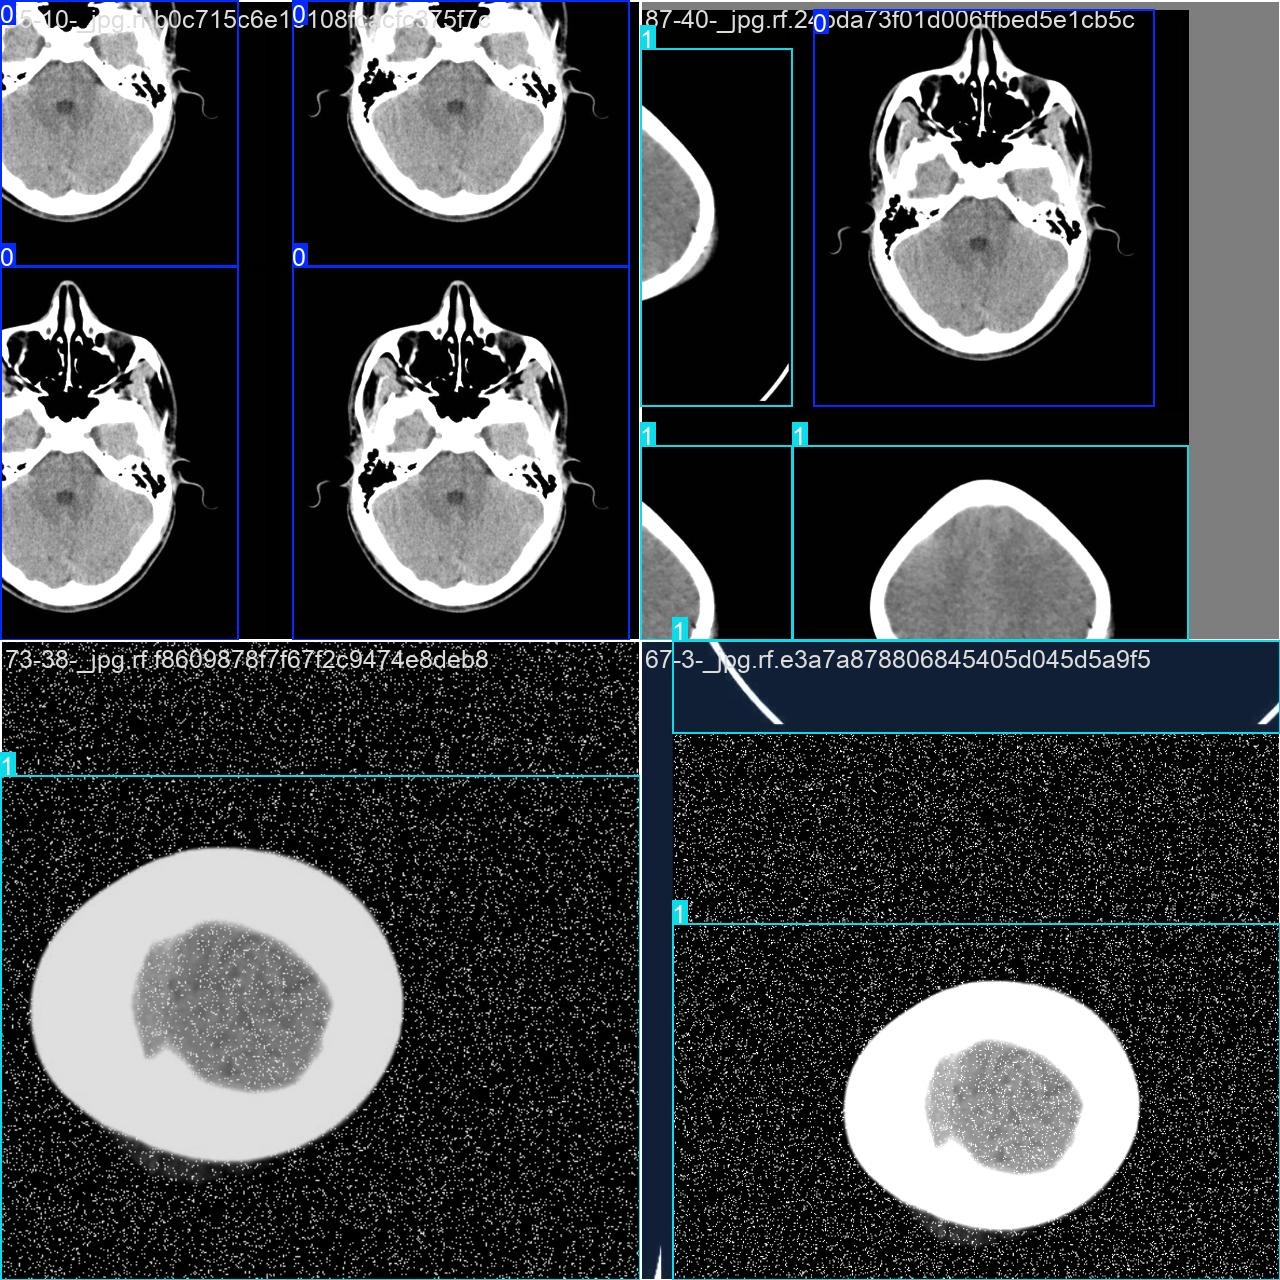

部分数据集图像如下图所示:

部分标注如下图所示:

本研究采用了涉及脑中风的数据集,并通过Labelimg标注工具对每张图片的目标边界框及其类别进行了标注。在此数据集中利用YOLOv8n模型进行了训练工作。经过训练后,在验证集中进行了全面的性能评估和对比分析。整个流程主要分为三个环节:数据准备、模型训练和性能评估阶段。本次标注任务主要关注的是脑中风相关类别问题。该数据集中共有6118张图片,在各个分类领域具有均衡分布特征